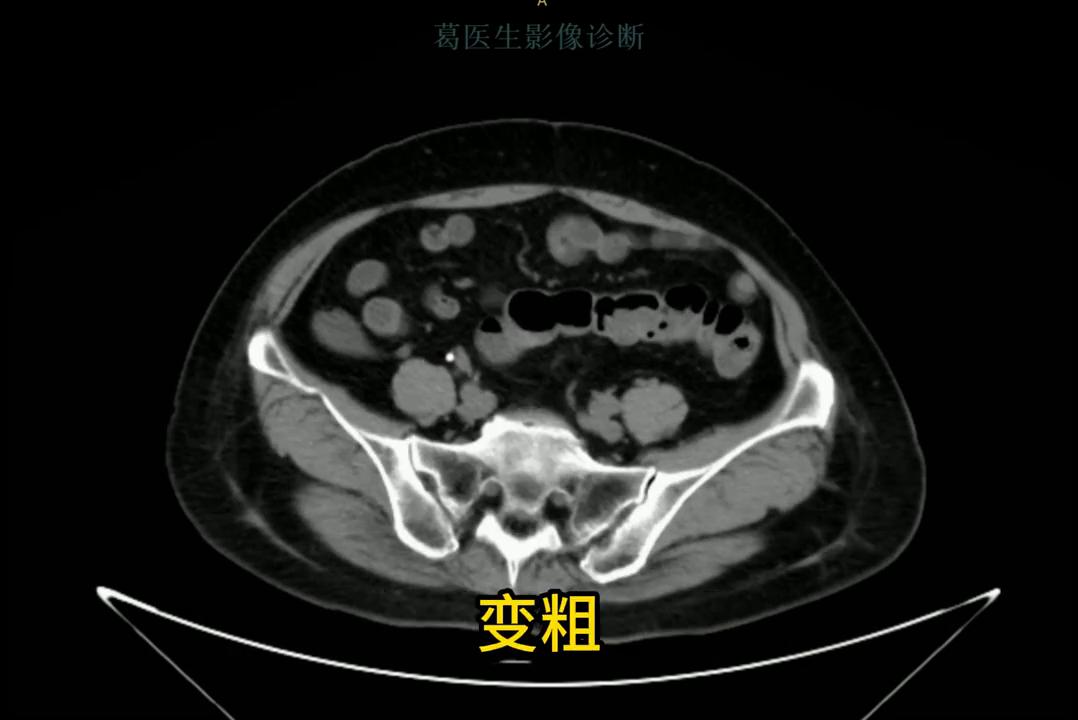

再往下走,重要的结构包括肛门,肛门区就是有一些门脉,胆管,胆总管,如果是肝硬化,门脉就会变粗,变粗环境会增宽。再往下面走就是胃,胃里面有什么?往下走是胃窦,然后是十二指肠球部,十二指肠球部这个地方容易长一些,胃溃疡,胃炎什么的都在这。

·然后走到后面这个地方,就是回肠的末端连连着盲肠,这是盲肠,盲肠往上走,升结肠,盲肠还连着一个重要的结构,一个一个盲端的肠肠管,这个比较长的一个小小的阑尾炎,要看阑尾炎总在先找到阑尾,这就是阑尾,阑尾如果阑尾炎就会变粗,里面可能有些会出现一些积液。然后顺着横结肠往上走,结肠肝曲,这个位置比较固定,就是看到肝脏下方一样有一个结肠那样的结构,那就是肝曲,位置一般不会变,其他部分就容易变动。